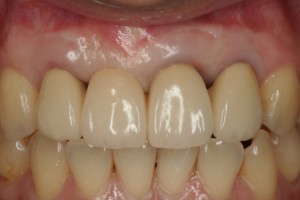

その後、歯肉の手術を行い歯肉のライン、歯の大きさのバランス、色や形態を合わせ完成となりました。歯肉も厚みを増し簡単に歯肉退縮しないようになっています。